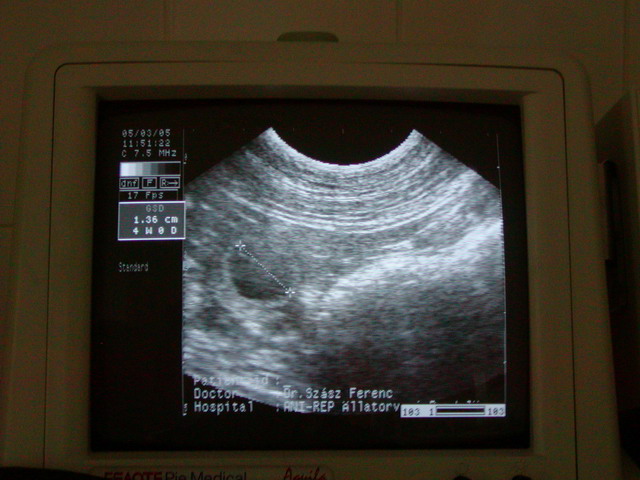

here we are with 21 days on the ultrasound-picture !